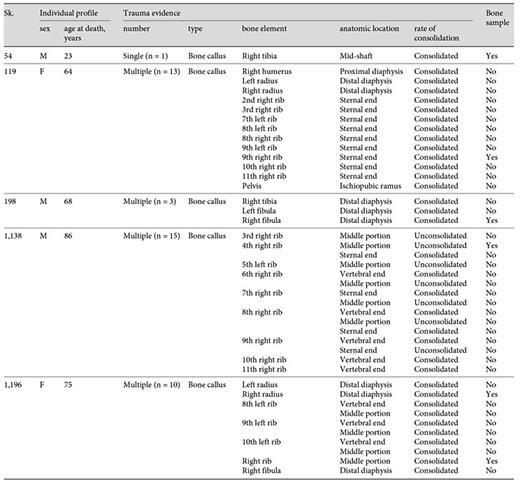

Histomorphology of the Bone Callus

The histological analysis of the 6 bone samples showed a well-preserved bone microanatomy with good bone birefringence. Some structural differences were found when the bone calluses were compared (table 4).

Evaluation of the histological features of the bone callus by individual, sample, healing stage, and type of trauma diagnosis

With regard to the Sk. 119 rib callus, no evidence of a cortical bone break was observed. Actually, the cortex exhibited a mature structure composed of numerous rows of osteons and interstitial lamellae. In the upper and lower edges of the pleural surface, a clear separation between the cortical bone and the patches of periosteal new bone was noticed. This level of microstructural organization was clearly distinguishable from the mesh-like pattern of interconnected lamellae and amorphous new bone formation noticed on the central portion of the pleural surface. Moreover, an accumulation of new bone in distinct stages of maturation was also observed. For instance, the deepest layers were formed by densely packed lamellae with small, elongated and erratic osteocyte lacunae, whereas the outermost ones were composed of a random structure with an immature appearance and were densely populated by circular osteocyte lacunae (fig. 11a-c1).

a Micrograph of the Sk. 119 right rib showing the cortical tissue composed of mature osteons (white arrowheads) and interstitial lamellae. A clear separation between the periosteal circumferential lamellae and a more disorganized periosteal new bone formation (white asterisk) is visible. b Segment exhibiting several rows of osteons (white arrowhead) intersected by sheets of lamellar bone with variable density (black arrowheads). Note the presence of a lumpy deposit of periosteal new bone (white asterisks). c Periosteal new bone formation exhibiting several degrees of bone organization (black arrowheads; circle 1). Multiple osteons are visible at the cortical level (white arrowhead). c1 Detail of the previous figure showing the inner layers composed of well-defined lamellae with small and elongated osteocyte lacunae and the outmost layers with a general lack of bone organization and populated by large and rounded osteocyte lacunae. Polarized light. Magnification ×40; ×100.

a Micrograph of the Sk. 119 right rib showing the cortical tissue composed of mature osteons (white arrowheads) and interstitial lamellae. A clear separation between the periosteal circumferential lamellae and a more disorganized periosteal new bone formation (white asterisk) is visible. b Segment exhibiting several rows of osteons (white arrowhead) intersected by sheets of lamellar bone with variable density (black arrowheads). Note the presence of a lumpy deposit of periosteal new bone (white asterisks). c Periosteal new bone formation exhibiting several degrees of bone organization (black arrowheads; circle 1). Multiple osteons are visible at the cortical level (white arrowhead). c1 Detail of the previous figure showing the inner layers composed of well-defined lamellae with small and elongated osteocyte lacunae and the outmost layers with a general lack of bone organization and populated by large and rounded osteocyte lacunae. Polarized light. Magnification ×40; ×100.

Despite the morphology of the outer shell of the Sk. 119 rib callus, which resembles a consolidated fracture, the histological study showed an unremodeled architecture compatible with a subperiosteal hematoma eventually caused by periosteum detachment, bleeding, and new bone formation through activation of the osteogenesis process. Nevertheless, a case of an incomplete microfracture cannot be completely excluded from the present diagnosis. The microstructure of hematoma is variable, ranging from thin layers that resemble a slip-like cover to relatively short, bulky bone trabeculae with extensive bridging, arc-like formation, and/or multiple layers [35,36,37]. In the case under discussion, the presence of tissues in distinct stages of maturation: immature and more disorganized bone/isodiametric osteocyte lacunae (outer layers) and lamellar bone/flattened osteocyte lacunae (deepest layers) seem to indicate that the bone lesion was undergoing remodeling at the time of death. Little can be said about the elapsed time after hematoma formation; nevertheless, and during fracture repair, the remodeling of woven bone into longitudinally oriented lamellar bone is observed to occur 14-21 days after injury [48]. Independently of the diagnosis, the presence of 9 rib calluses (n = 6, right ribs; n = 3, left ribs; table 2) seems to indicate that this female was exposed to chest trauma that caused a minor tissue disruption in the 9th right rib.